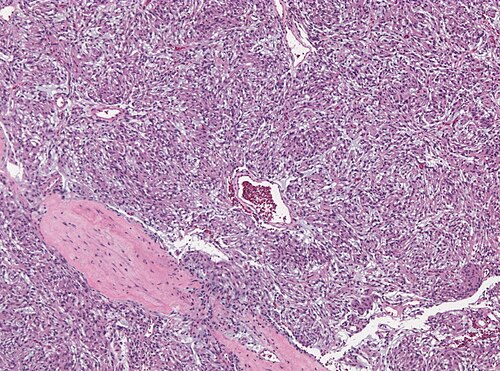

Provided clinical history

34 year old female with sudden seizures.

Site

Temporal lobe.

Primary image

Low magnification. H&E stain.

Differential diagnosis

Metastasis, Meningioma, Chordoid Glioma, Chordoma

The tumor has contact to the leptomeninges.

Spindle shaped in a mucoid background. Was EMA immunostain positive?

Diagnosis

Chordoid meningioma WHO grade II

Comment: Most meningioma subtypes correspond to WHO grade I. Chordoid meningioma is one of the variant that - even in absence of atypia or mitoses - is graded WHO II.